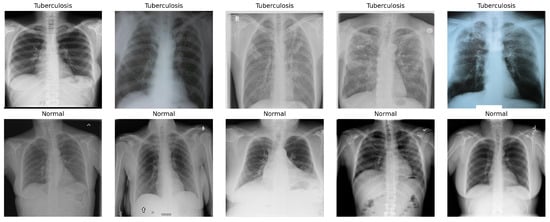

1. Tuberculosis (TB) Chest X-ray Dataset: This dataset, Figure 6, was compiled through a collaboration between Qatar University, the University of Dhaka, and medical institutions in Bangladesh and Malaysia. It consists of 700 publicly available TB-positive chest X-ray images and approximately 3500 normal cases [49]. These images were collected from various clinical settings and provide a valuable benchmark for testing cross-condition model generalization beyond COVID-19.

Figure 6. Sample images of Tuberculosis (TB) Chest X-ray Dataset.